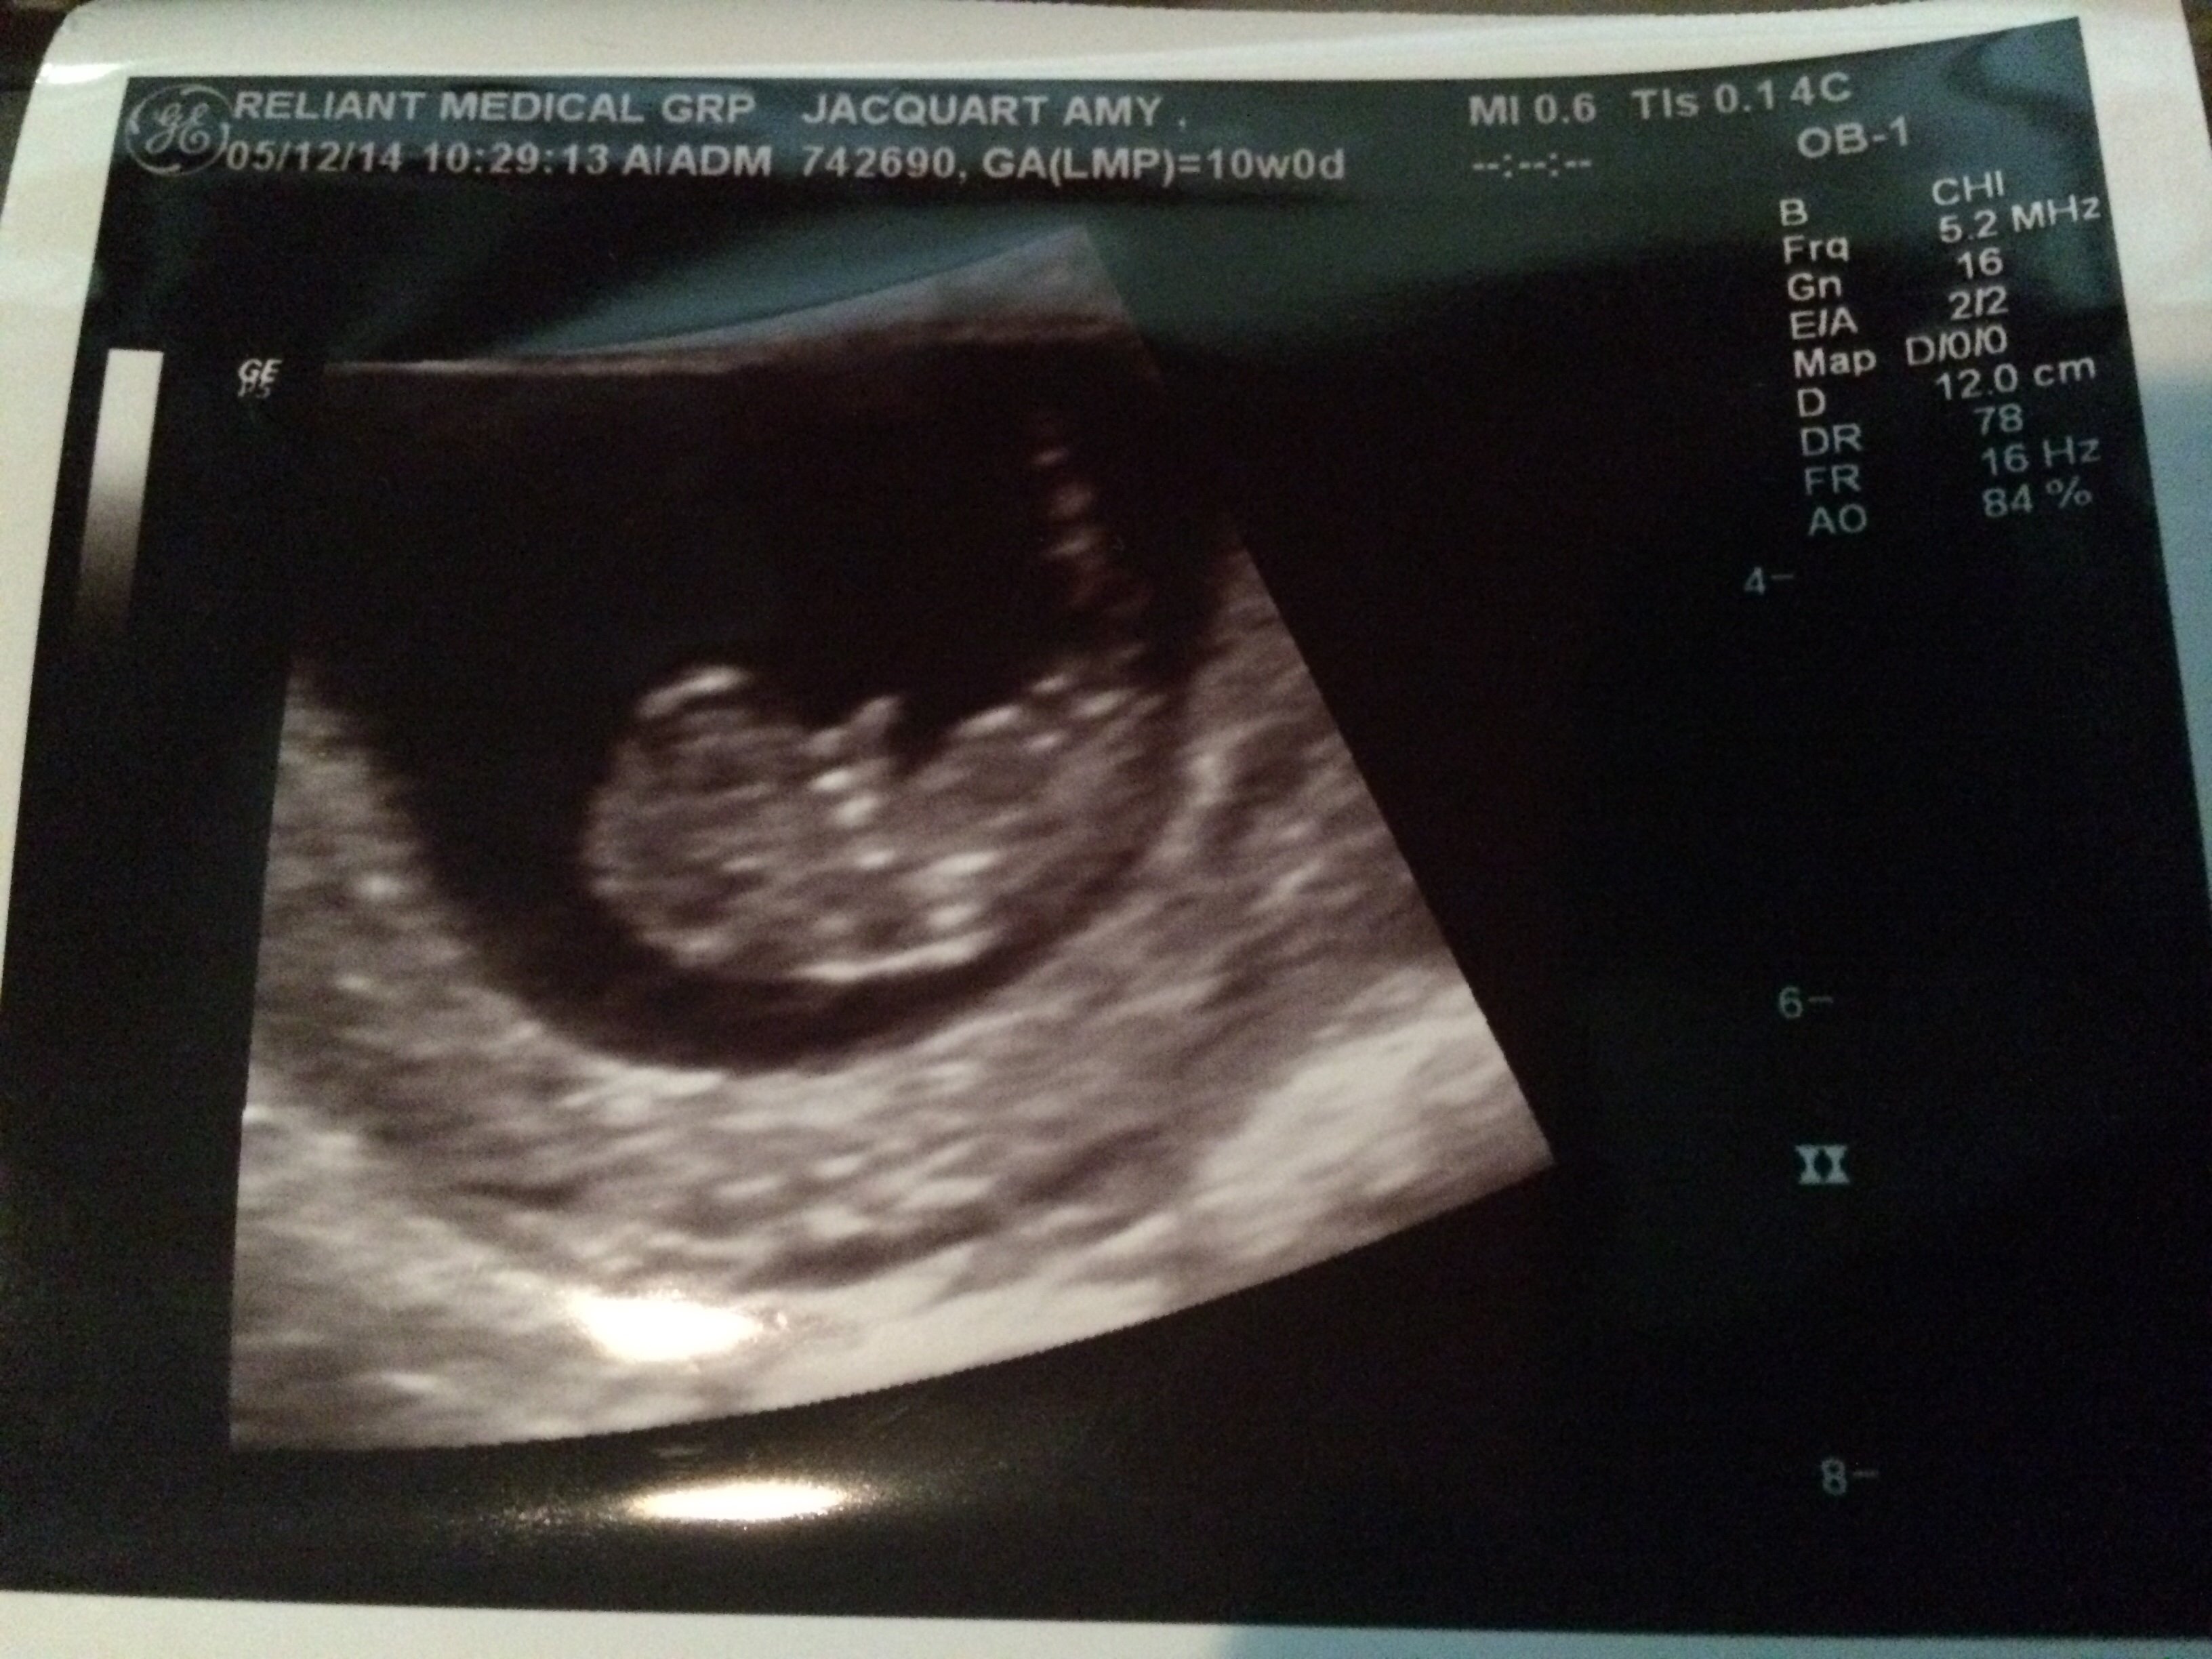

Just left my ultrasound appointment and relieves doesn't even begin to cover it! At my last appointment there was some confusion regarding how far along I was so I was sent in for a dating ultrasound. My doctor told me it felt like I was 8 weeks but I thought I was 10. Well I was right!!

Here's some photos of my little bean! Heart rate was 180!

Such a great feeling to see him/her on that screen!!!